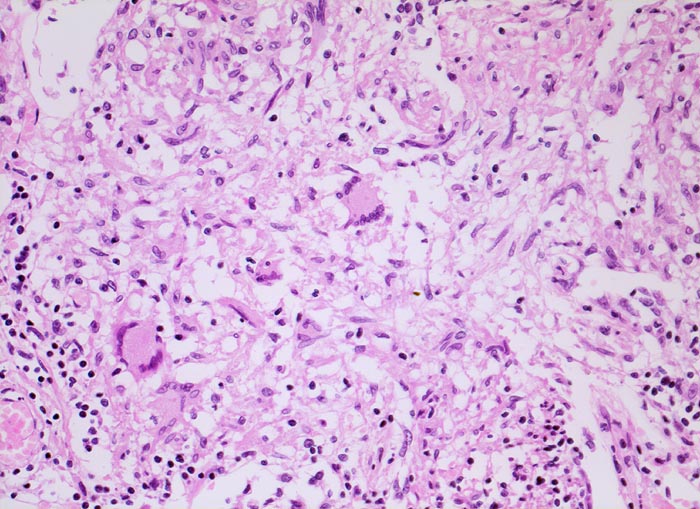

• Granulome mit zentraler käsiger Nekrose mit Kerntrümmern umgeben von einem Epitheloidzellwall und einem äusseren blauen Saum von Lymphozyten.

• Schlanke spindelige Epitheloidzellen und einzelne Riesenzellen vom Langhanstyp mit peripher hufeisenförmig angeordneten Kernen.